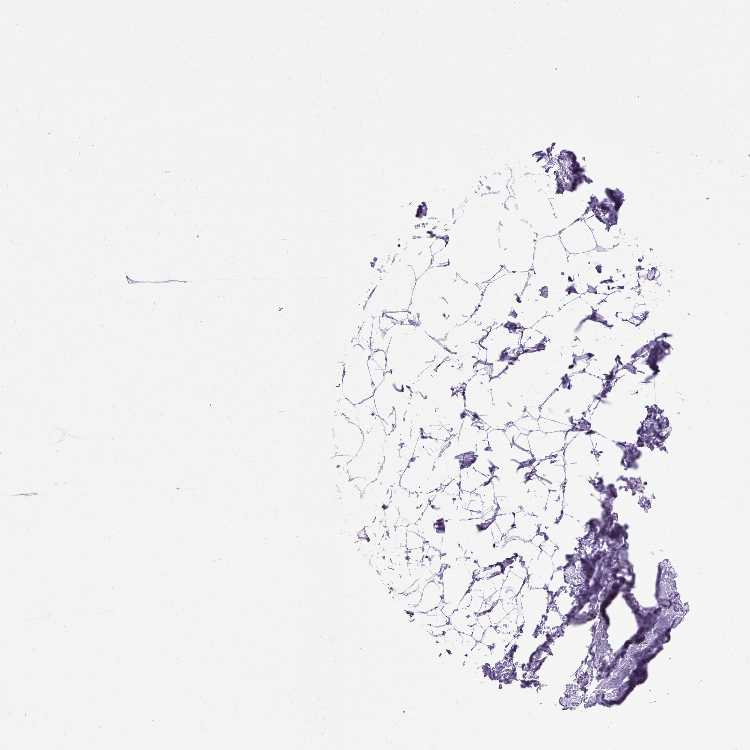

BREAST - Antibody stainingi

Antibody staining in the annotated cell types in the current human tissue is reported as not detected, low, medium, or high, based on conventional immunohistochemistry profiling in selected tissues. This score is based on the combination of the staining intensity and fraction of stained cells.

Each image is clickable and will lead to virtual microscopy that enables deeper exploration of all samples and also displays staining intensity scores, fraction scores and subcellular localization as well as patient and tissue information for each sample.

Antibody HPA035483Antibody CAB010762

Adipocytes Not detectedNot detected

Glandular cells HighMedium

Myoepithelial cells Not detectedMedium